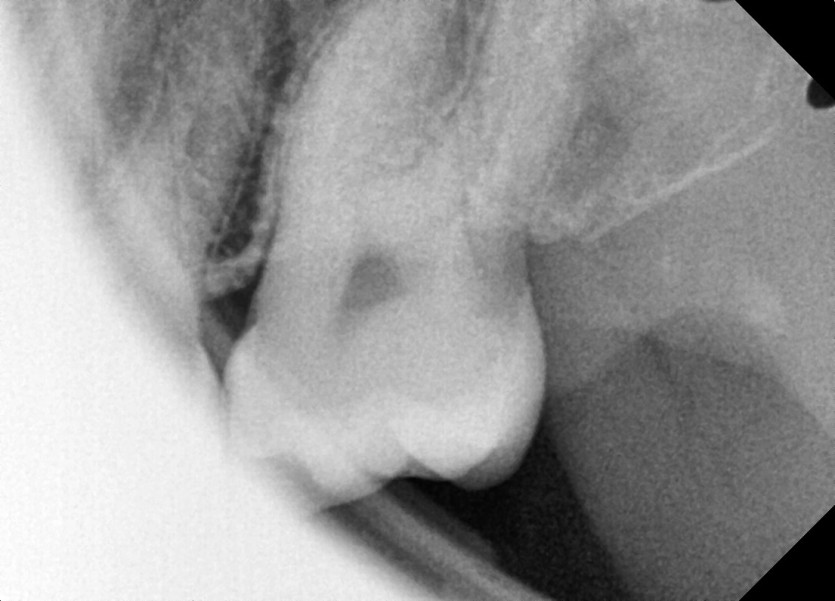

#28,38 사랑니 발치

구강 외과 전문의가 당일 발치했습니다.